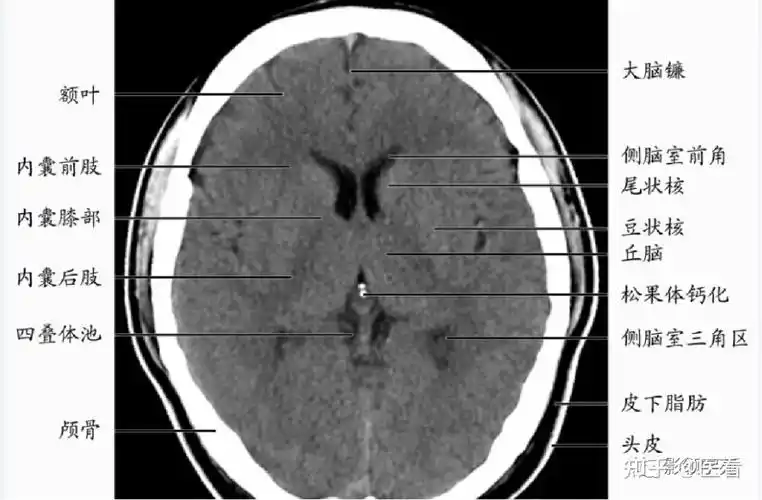

基底节区:概念不清. 可能包括:基底节,黑质,红核,及其周围白质区域.